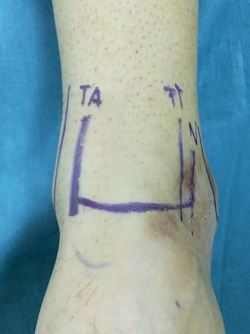

La pierna se coloca en una pernera que sujeta la tibia paralela al suelo y con una posición del tobillo en anteroposterior respecto al suelo, dejando el tobillo libre en el aire, lo que permite una gran zona de trabajo alrededor del mismo (Figura 1).

Una vez colocado en la posición anteriormente descrita, marcamos todas las estructuras anatómicas (maléolos, nervio peroneo superficial, tendón peroneus tertius/extensor del 5.º dedo y tendón tibial anterior) que nos permitirán realizar los portales minimizando el riesgo de lesionar estructuras neurovasculares y tendinosas(10)(Figura 2).

Figura 2. Marcaje de la anatomía del aspecto anterior del tobillo, para protección de la misma y facilitar el trabajo.